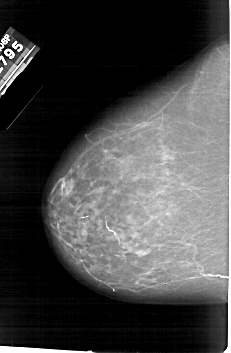

A_1895_1.LEFT_CC

LEFT_CC LINES 6346 PIXELS_PER_LINE 4141 BITS_PER_PIXEL 12 RESOLUTION 43.5 NON_OVERLAY